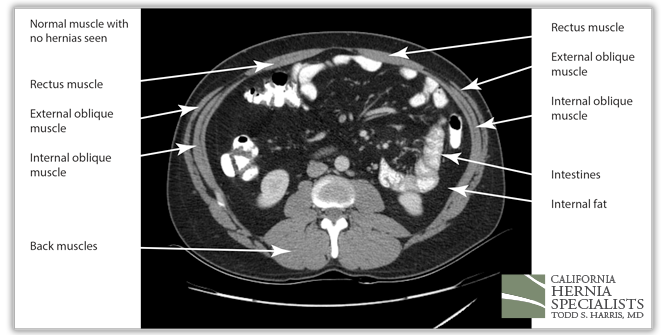

The CAT scan image above shows normal muscles of the abdominal wall with no evidence of a hole, or a hernia.

The 3 CAT scan images below show the patients normal muscles above the hernia, then a large hernia defect or hole in the muscle, and then the normal muscles again below the hernia defect.

The above image shows the upper part of this patients abdomen. No hernia is seen here; only normal muscles.